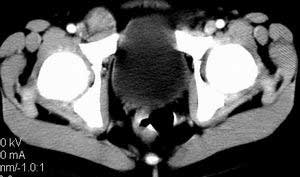

| 患者,男,9岁,因右下腹包块入院,血象不高,不规则发热,常超40度。 平扫: ![]() ![]() ![]() ![]() ![]() ![]() ![]() ![]() ![]() ![]() ![]() ![]() ![]() ![]() ![]() ![]() ![]() ![]() 增强: ![]() ![]() ![]() ![]() ![]() ![]() ![]() ![]() ![]() ![]() ![]() ![]() ![]() ![]() jiajie发言:骶椎右前区不规则软组织肿块,边缘光整,密度均匀,增强后均匀强化,右腹股沟区可见肿大淋巴结,临床有时发热,考虑淋巴瘤,儿童盆腔肿瘤应与神经母细胞瘤和横纹肌肉瘤鉴别。 longzhanghui发言:印象:盆腔右后壁不规则软组织肿块,并向前延伸.似为多个肿块融合,呈中等强化.初步考虑淋巴瘤. 听蝉观竹发言:右侧髂内、外组淋巴结肿大,从其形态和融合的情况看,同意大家意见-----考虑恶性病变,但是9岁男孩还要注意检查睾丸情况,有无隐睾? 常常类似情况是隐睾发生精原细胞瘤淋巴结转移,这个病例也要注意这一点!!! 广东凌发言:大家好,在这里我想说一下个人观点,我建议上传图片的同志能否辛苦一点就是把病史和图片都上传完整一点,比如这个病人的腹膜窗,并且这个病人的肠道的准备也是不怎么好,就从现有的质料看:病灶属于淋巴结肿大当无大的争议,有融合趋势,其内无坏死,边缘强化为主,故考虑:淋巴瘤!建议用腹膜窗看一下和肠道的关系! 阿圣发言:病灶属于淋巴结肿大当无大的争议,有融合趋势,其内无坏死,边缘强化为主,故考虑:淋巴瘤 结果是:淋巴瘤 病例来源:ct762。由宁静致远发布: http://www.radinet.com.cn/forum_view.asp?forum_id=4&view_id=2182 |